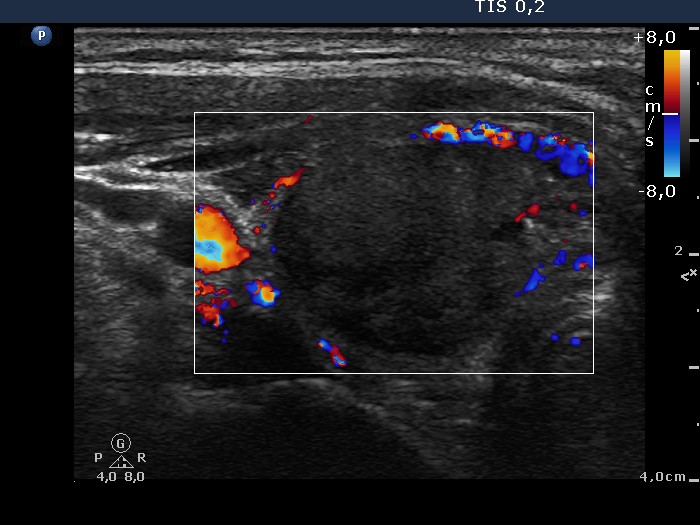

Ultrasonography: the thyroids were echonormal. There was an echonormal nodule occupying almost the entire right lobe. The lesion displayed a halo sign, cystic degeneration and presented perinodular blood flow.

5 sessions of sclerotherapy were performed. We demonstrate the 1st and 4th session.